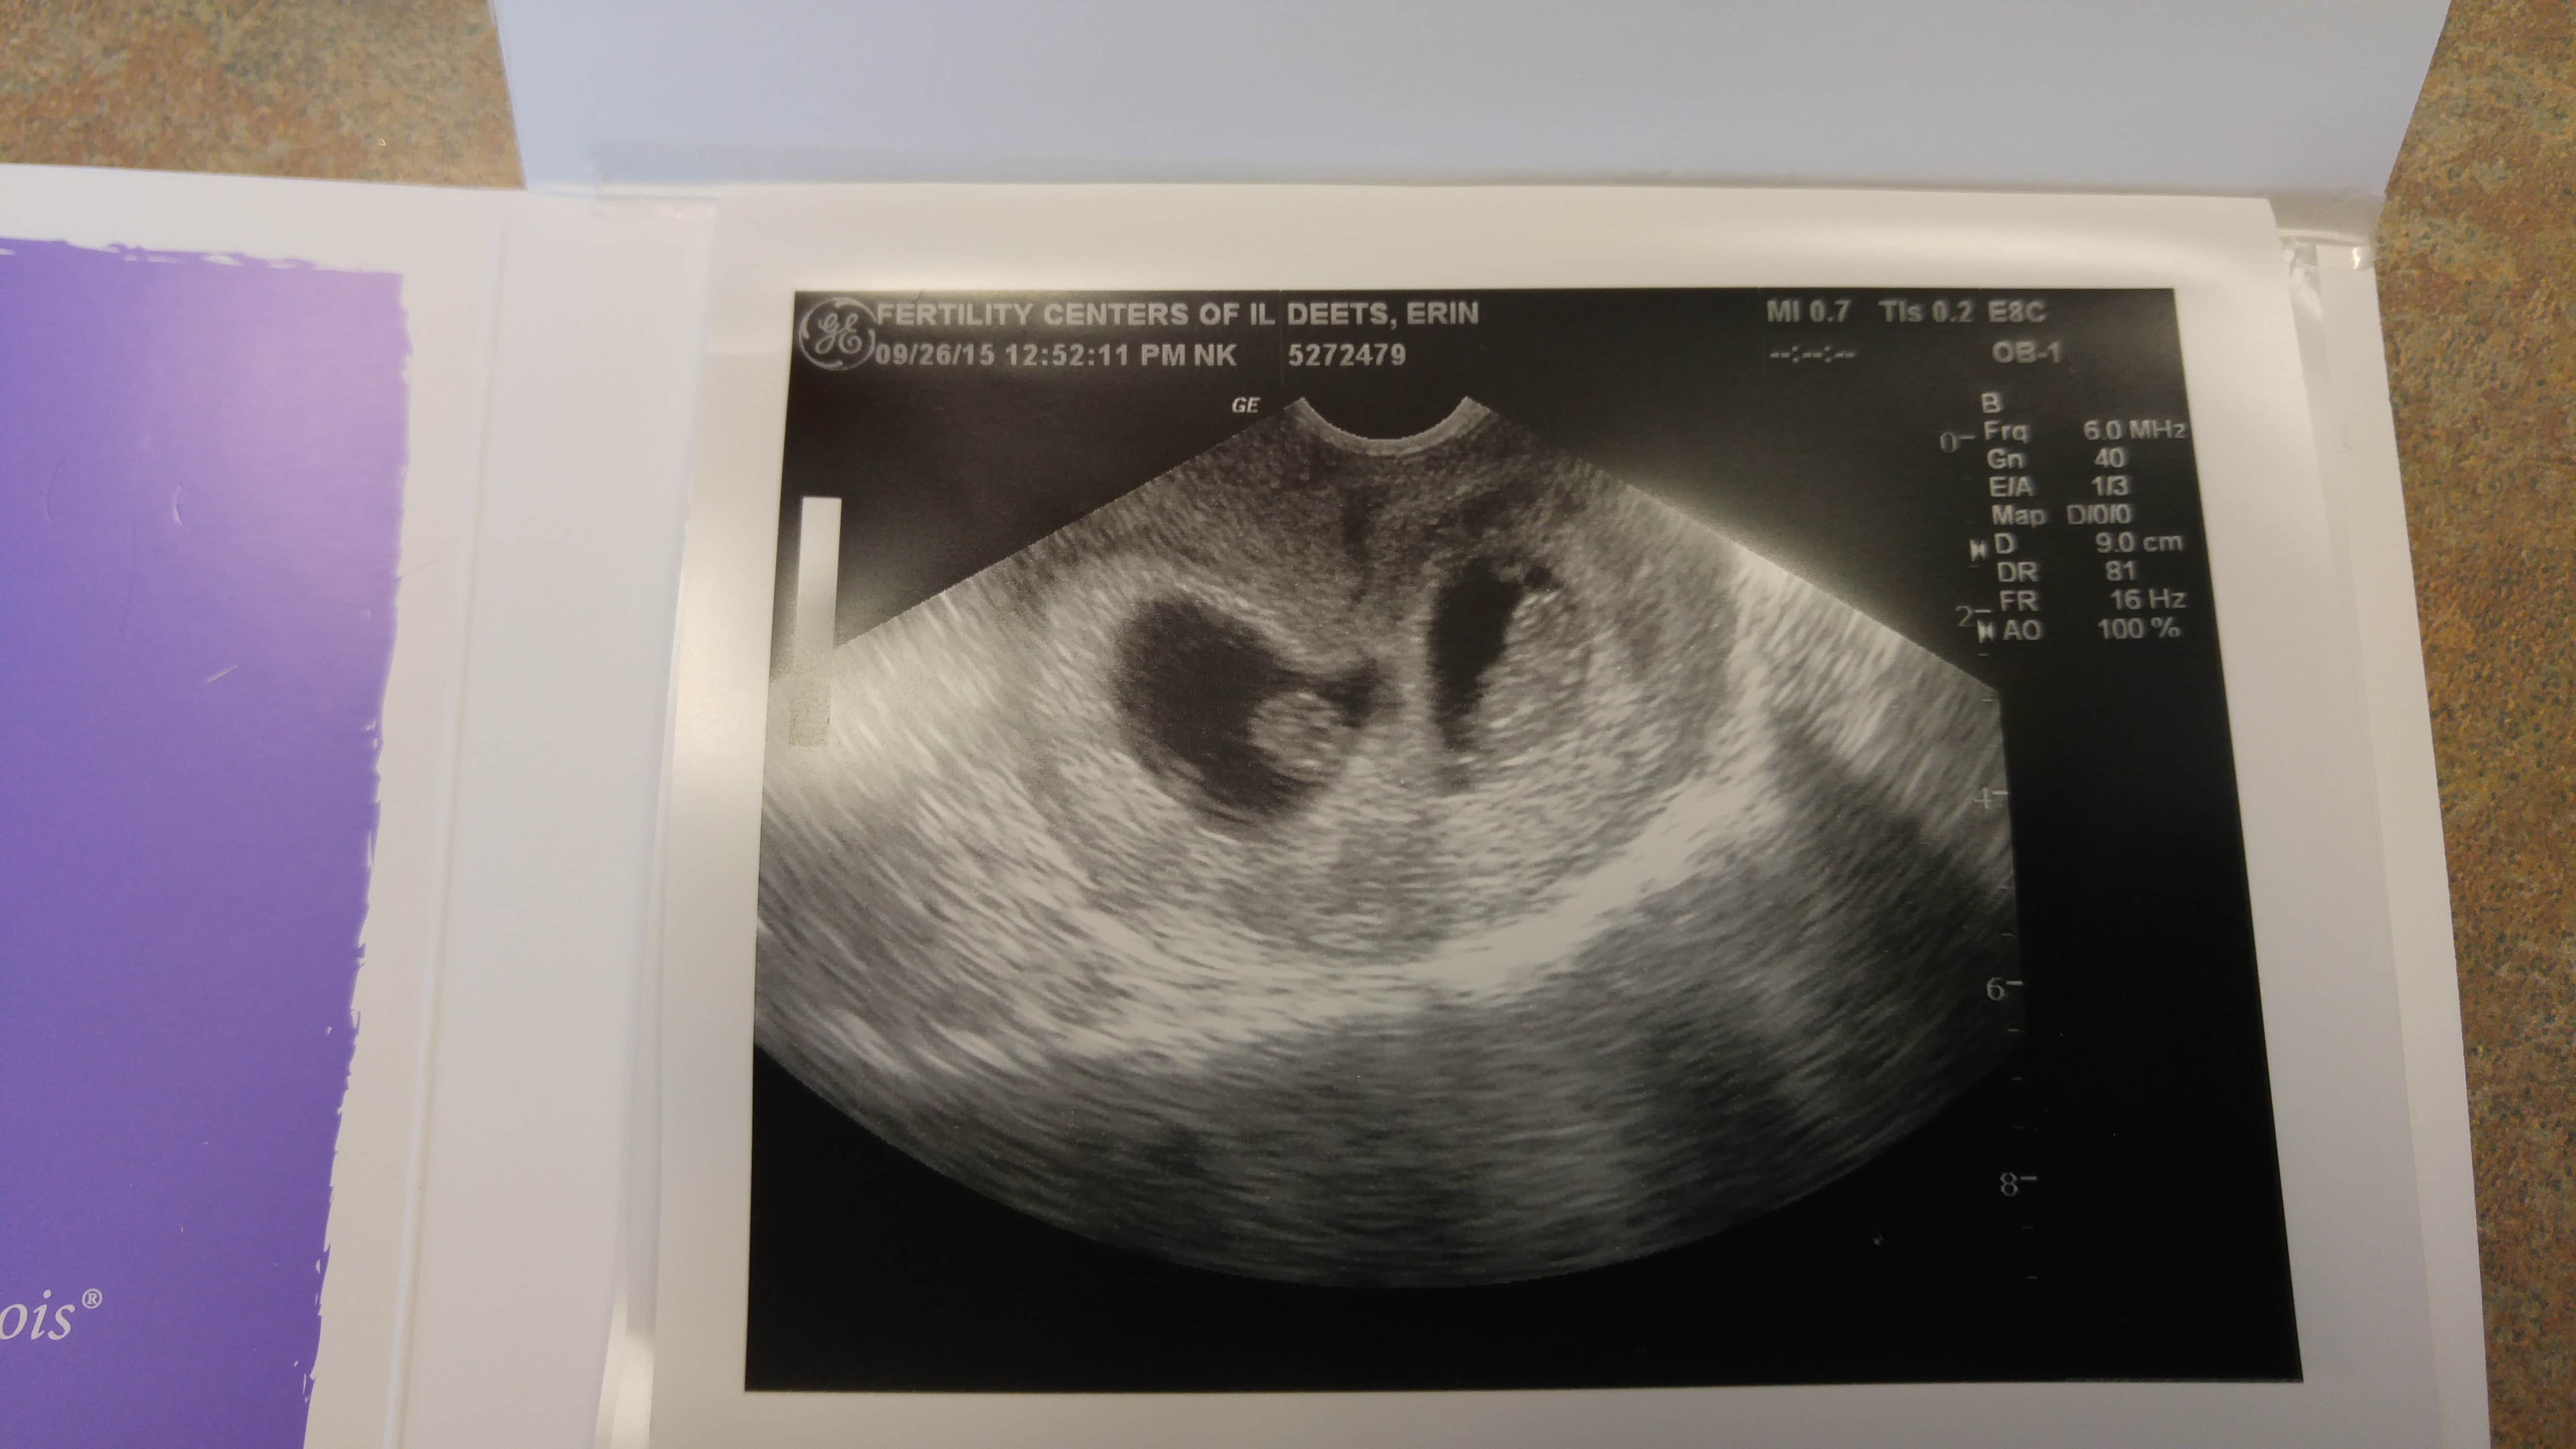

Ultrasound Photos of 9 Weeks Pregnant With Twins